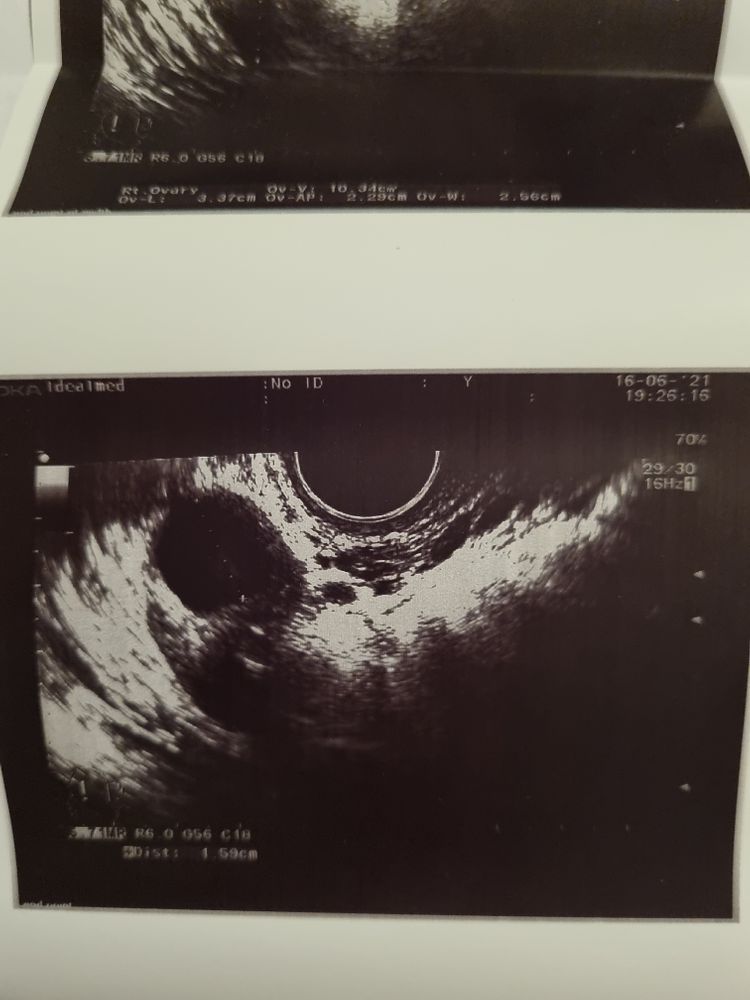

16.06 тянул ПЯ где и был доминантный. Вечером на фоликулометрии врач нашла только фоликул 16. Сказала,что возможно была овуляция, но это не точно,жидкости нет,и не похоже на жёлтое тело.